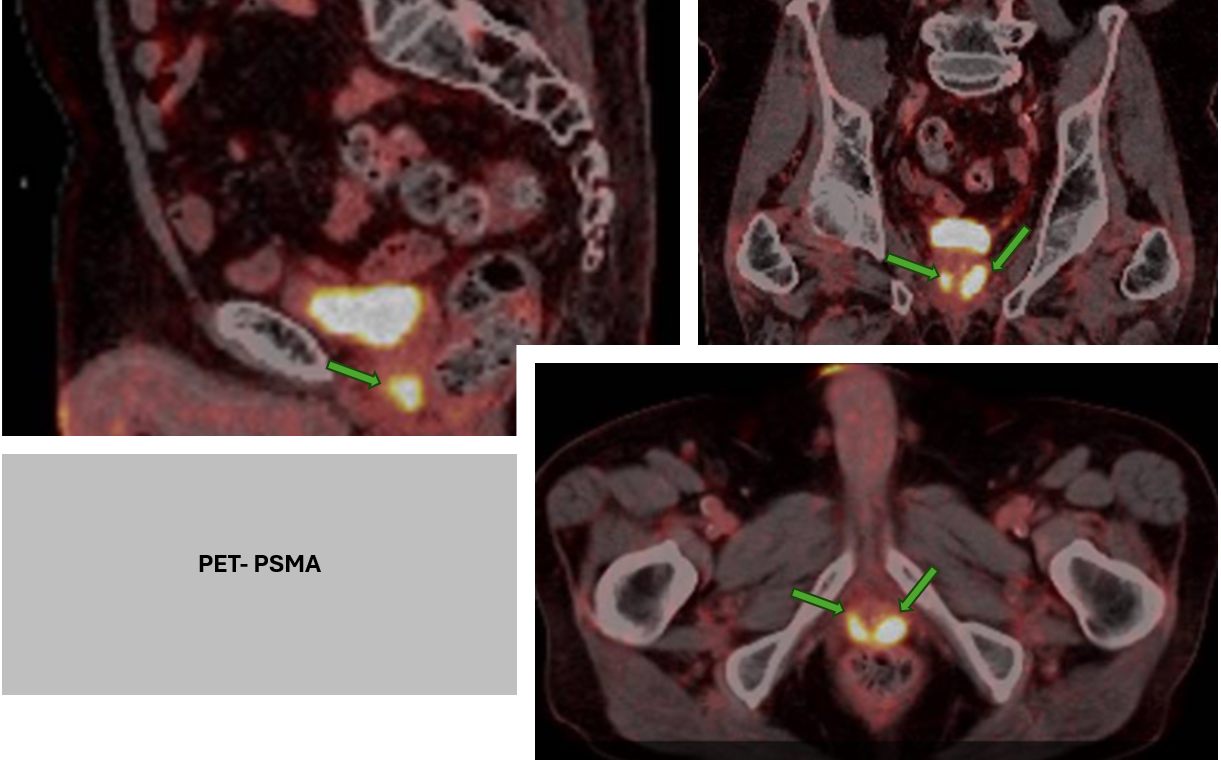

La técnica de PET-PSMA (Tomografía por Emisión de Positrones con trazadores dirigidos al PSMA) combina la imagen funcional propia del PET con un radiofármaco que se une específicamente a este antígeno. Esto permite localizar con gran precisión focos de enfermedad prostática activa, incluso en estadios donde otras modalidades de imagen como TAC o RMN podrían no ser concluyentes.

- Identificación de metástasis ocultas, tanto ganglionares como óseas, que pueden modificar radicalmente la estrategia terapéutica.

- Detección precoz de recurrencia bioquímica, incluso con niveles bajos de PSA.